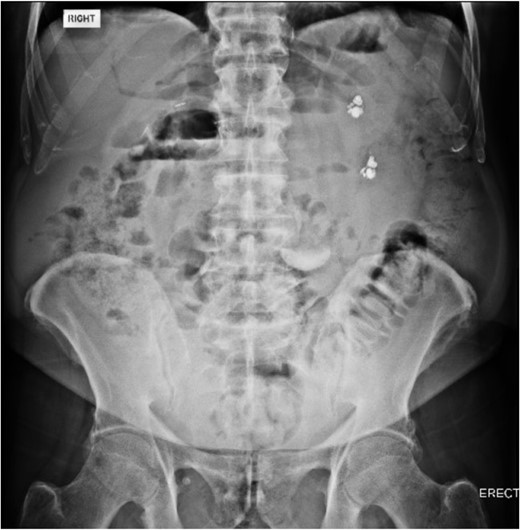

An 80 year old male presented to the emergency department after accidentally swallowing his hearing aids. On presentation he was pain free, hemodynamically stable, and had a soft abdomen. He had a background of type-2 diabetes, rheumatoid arthritis and diverticulitis. The hearing aids were powered by lithium battery. X-ray found two foreign bodies in the left upper abdomen (Fig. 1). After assessment in the emergency department, he returned home to await their natural passage. One hearing aid was found in his stools the following day, but he represented three weeks later as the second hearing aid remained unaccounted for. He underwent repeat abdominal x-ray and CT, which found the hearing aid retained within a presumed distal duodenal diverticulum (Figs 2 and 3). He was booked a push enteroscopy the following day.

Abdominal CT identifying one hearing aid in a jejunal diverticulum 3 weeks after initial presentation – coronal view.